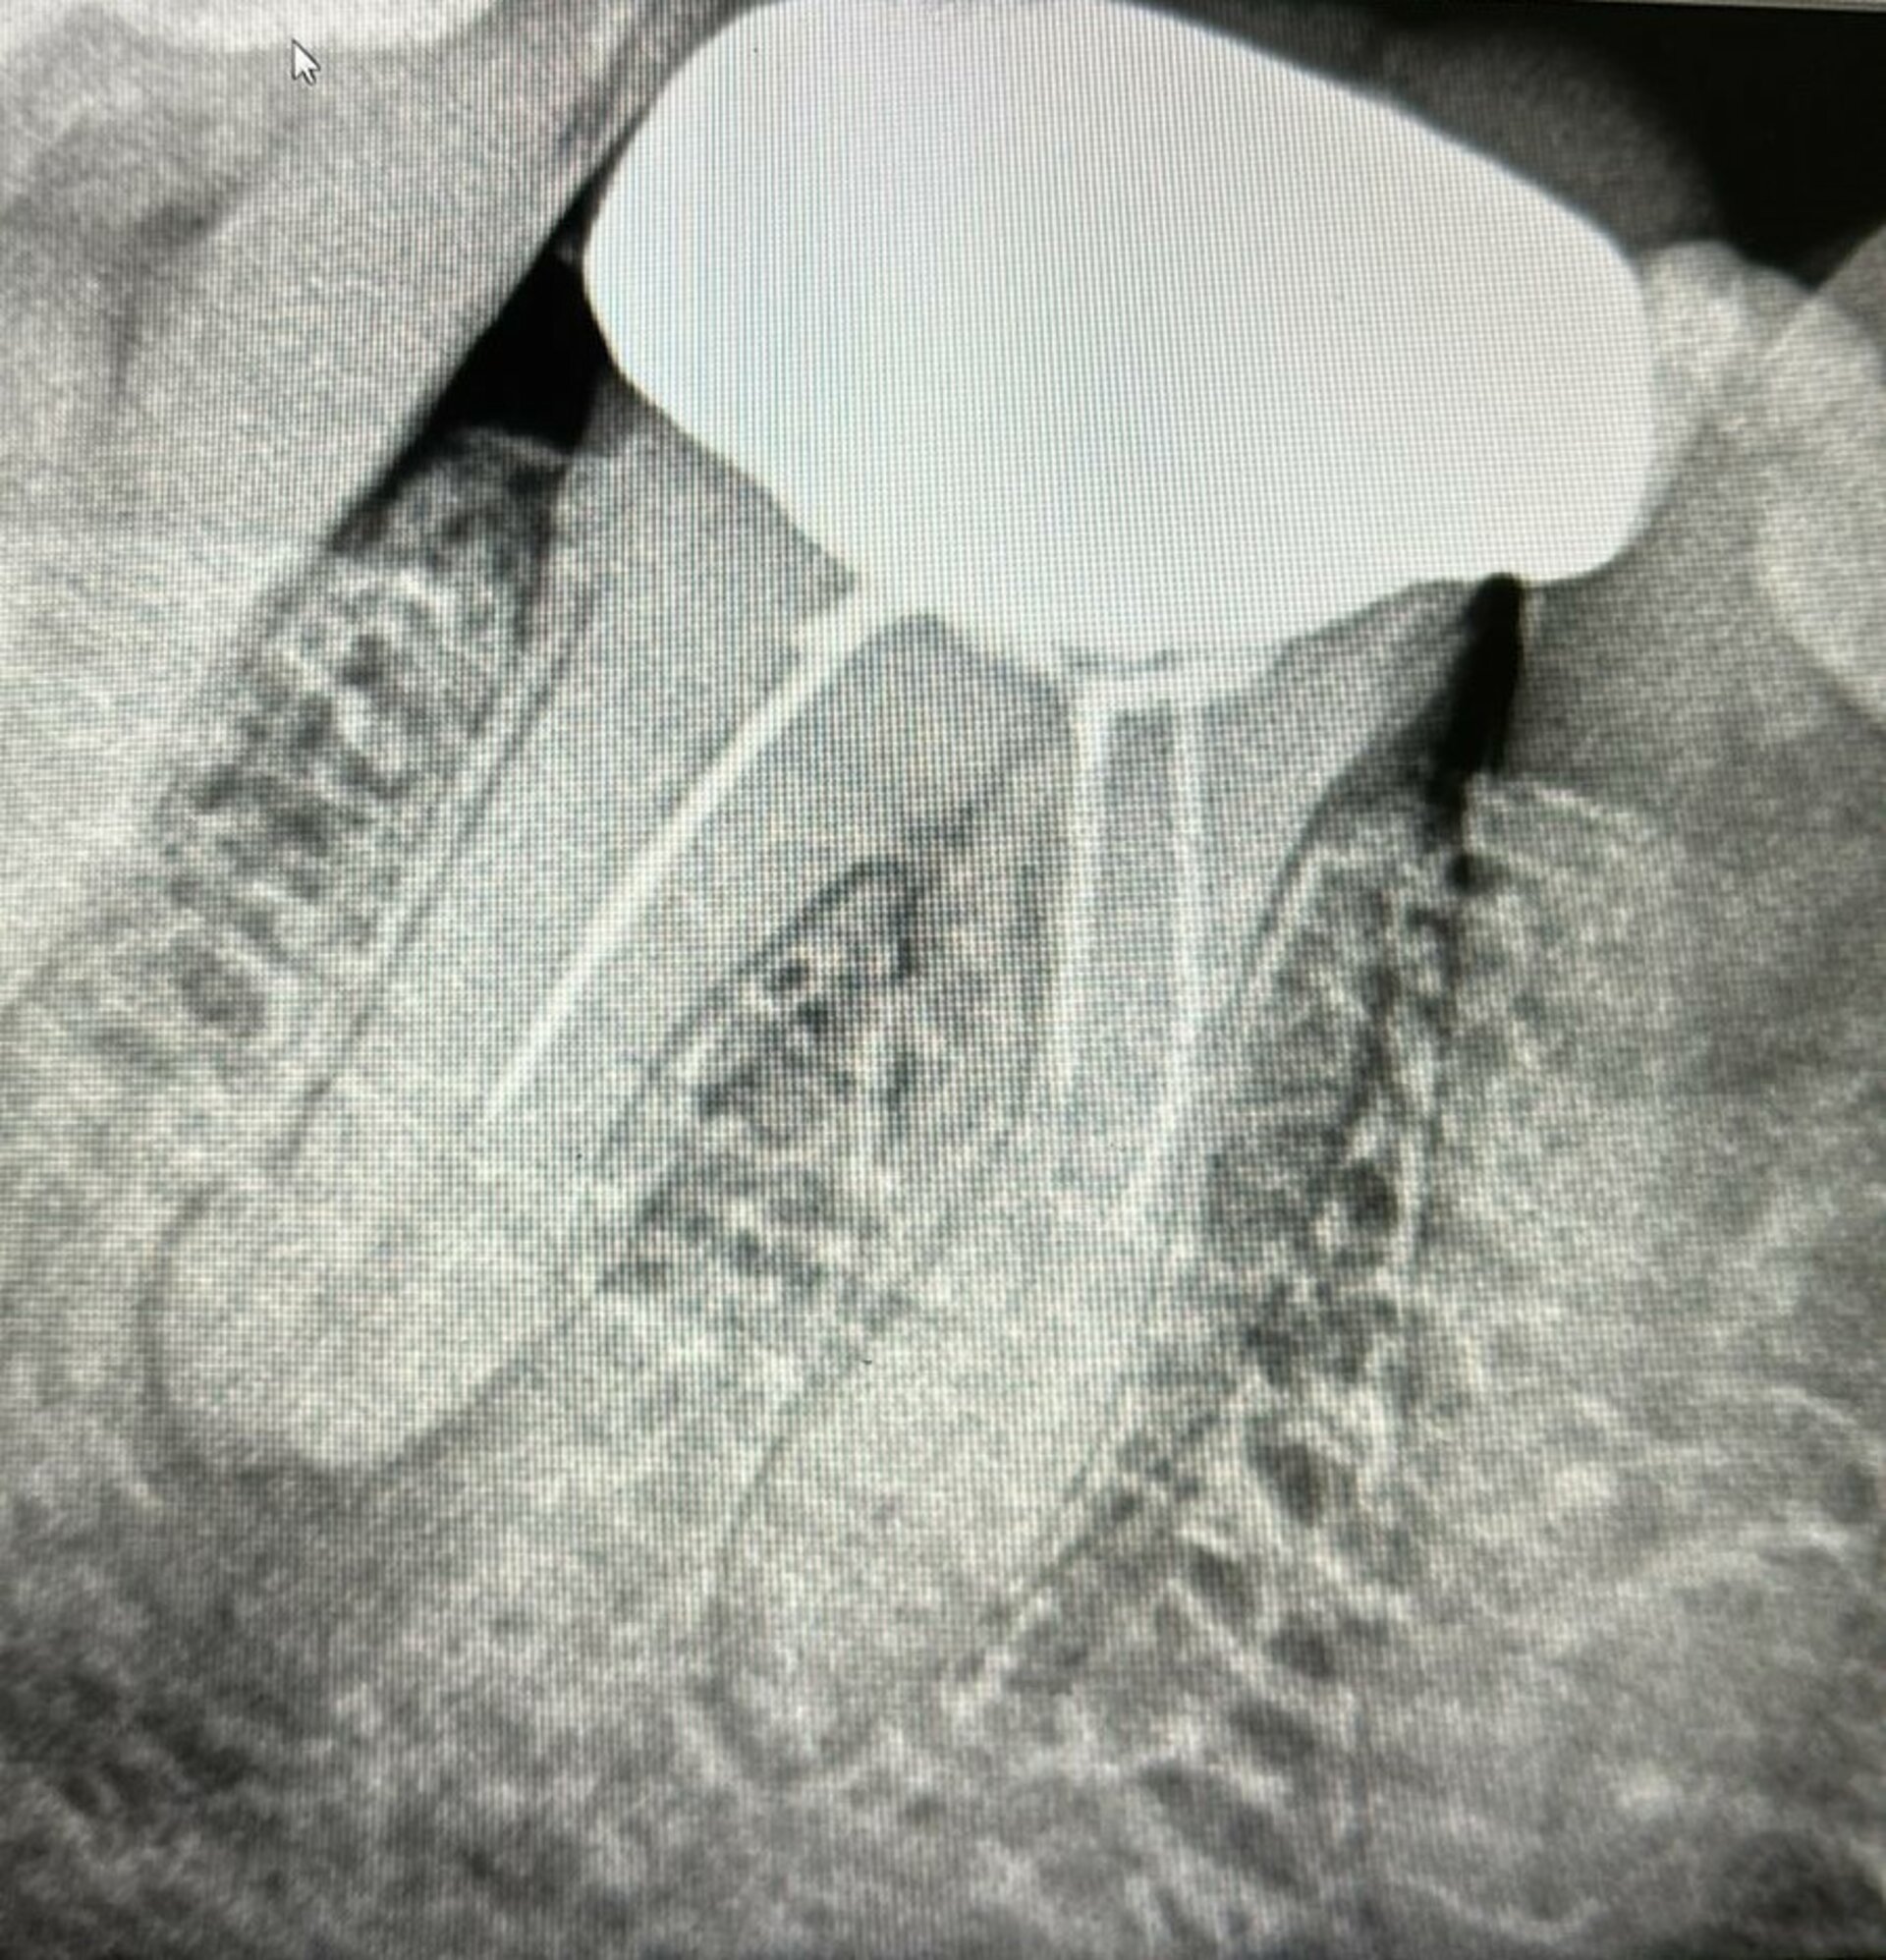

At Phadke Dental Clinic, Dr. Gautami Phadke recently treated a patient suffering from severe pain due to a failed root canal procedure performed elsew...